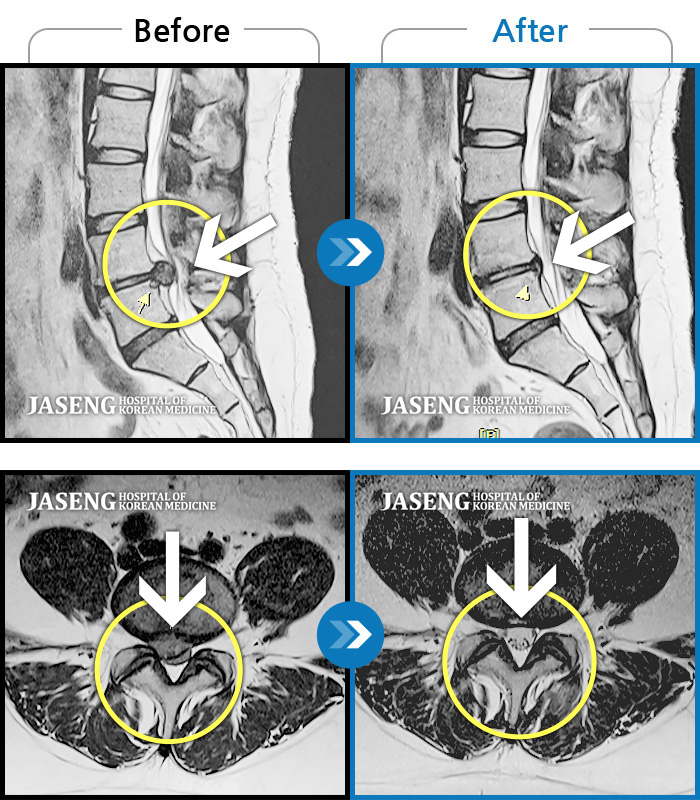

허리디스크

광주 · 김동은 원장

허리 통증과 양측 둔부부터 허벅지, 발목 부위 저리는 증상으로 내원하셨습니다.

촬영시기

2025.05.09 ~ 2025.12.18

2025.12.22